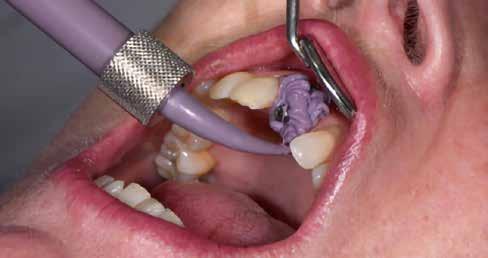

A digitális lenyomatvétel

A kezdetben említettük, célunk a digitális technológiák maximális kihasználása volt. Fontos volt számunkra, hogy semmilyen minőségi kompromisszumba ne kelljen bocsátkozni. A digitális lenyomatvétel a Kulzer cég cara i700-as intraorális szkennerével történt (4. kép). Mint számos ma használatos készülék, ez is egy optikai rendszer, amely minden, a kezelőorvos számára is látható területet beolvas. Akárcsak az analóg eljárásban, itt is szükséges a szulkusztágító fona-

5. kép: A preparált szituáció, előkészítve beolvasásra.